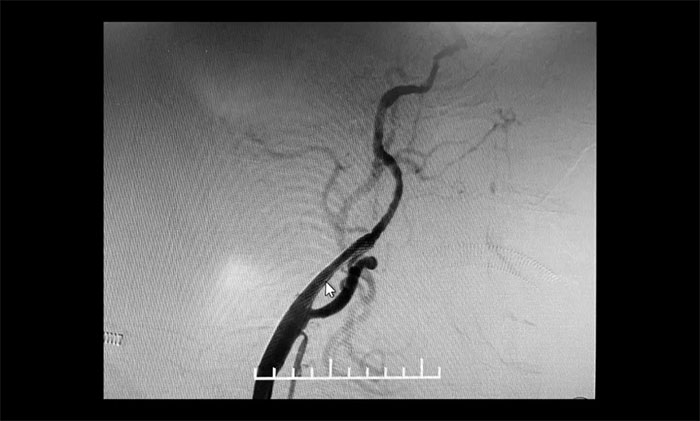

術(shù)后康復(fù)觀察一月余,于耀宇主任團(tuán)隊(duì)再次為曹老伯行右側(cè)頸動(dòng)脈支架置入及左側(cè)椎動(dòng)脈支架置入手術(shù)。術(shù)中造影顯示,右側(cè)頸內(nèi)動(dòng)脈起始段重度狹窄,狹窄長(zhǎng)度8mm左右。左側(cè)椎動(dòng)脈 V4 段重度狹窄,長(zhǎng)度6mm左右。運(yùn)用嫻熟扎實(shí)的技術(shù),在充分做好腦保護(hù)的前提下經(jīng)過(guò)多次球囊擴(kuò)張后,順利釋放支架于狹窄處。造影提示支架打開(kāi)良好,血管狹窄基本恢復(fù)正常,支架貼壁佳,支架內(nèi)血流通暢,遠(yuǎn)端血流良好。

▲ 術(shù)后,右側(cè)頸內(nèi)動(dòng)脈及左側(cè)椎動(dòng)脈狹窄明顯改善